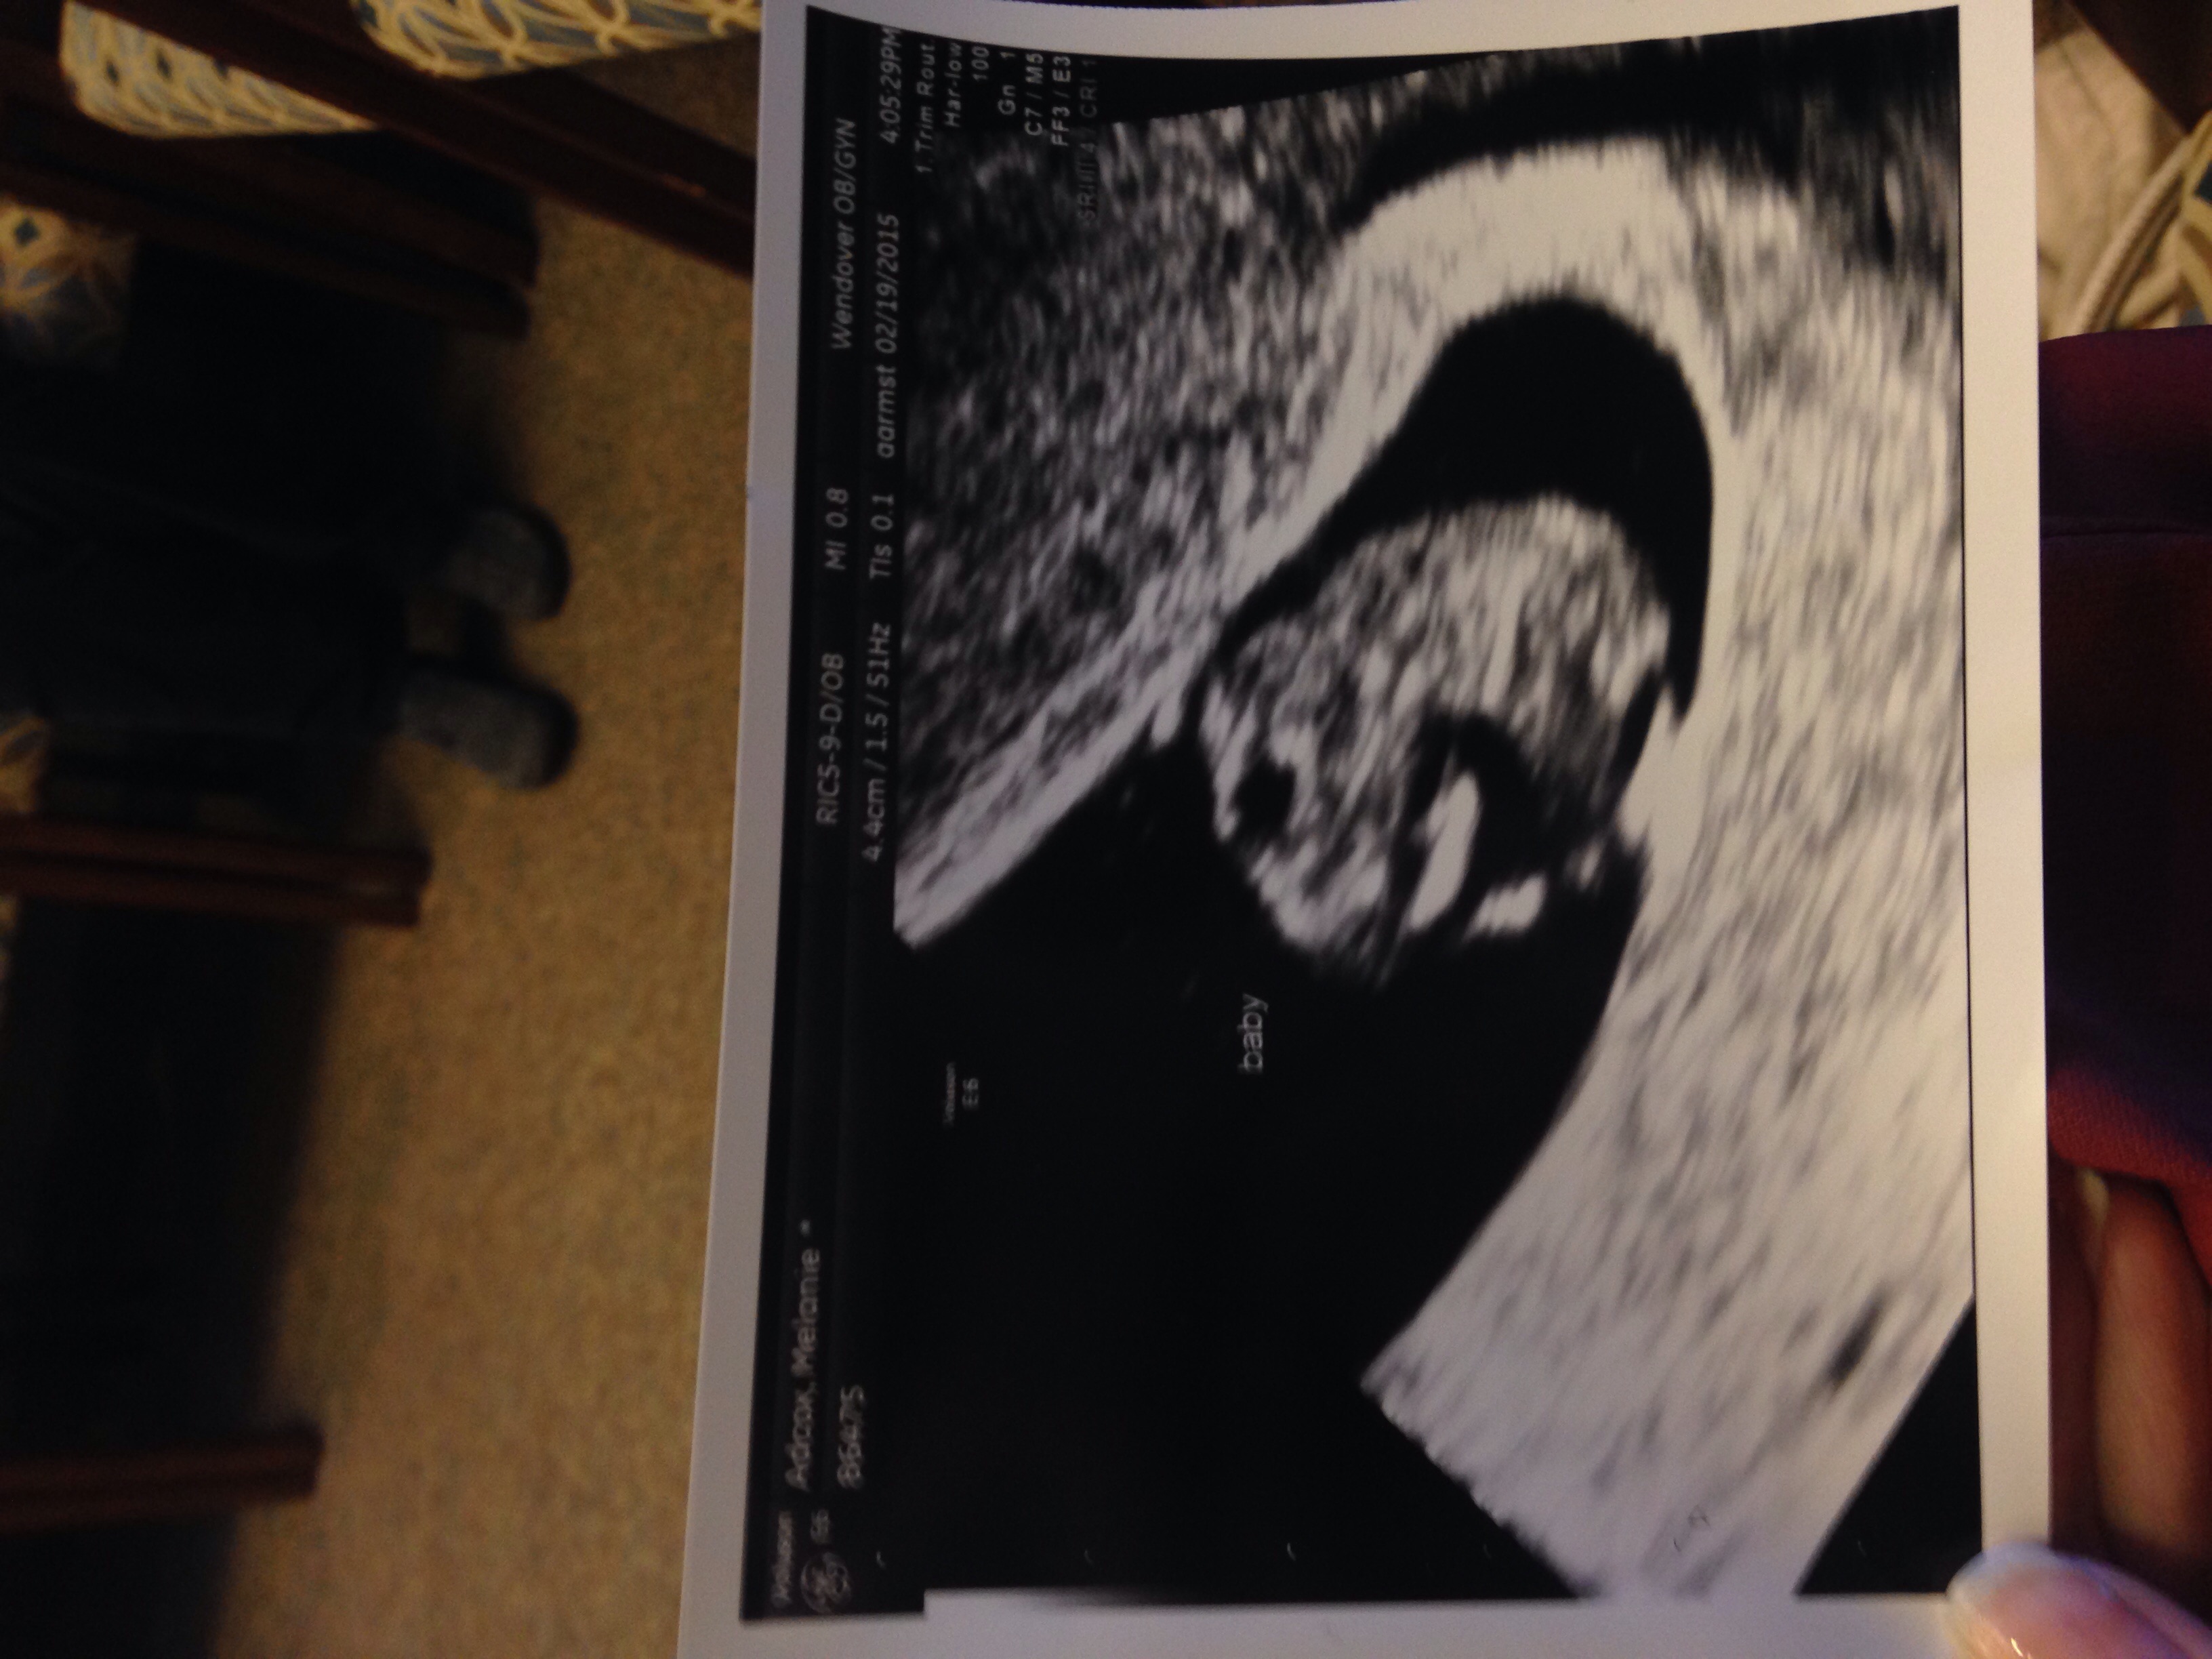

UPDATE - my first u/s is on page 1, first comment. This is my 10 week ultrasound (zoomed) baby is not this big lol!! First is head and body, second is full body! Baby was dancing and it was adorable!

First is head and body, second is full body! Baby was dancing and it was adorable!